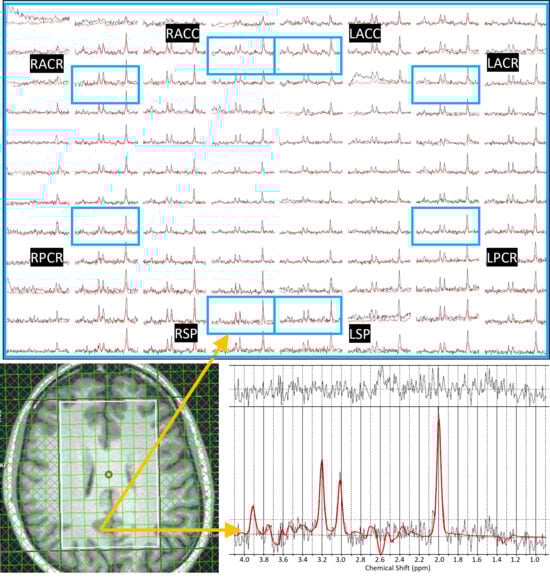

Association of Intracellular Microstructural and Neuropsychological Changes in HIV: A Pilot Validation of Trace Diffusion-Weighted Magnetic Resonance Spectroscopic Imaging Using Radial Trajectories

Background: Despite effective antiretroviral therapy, HIV-associated neurocognitive disorders (HANDs) remain prevalent, highlighting the need for sensitive biomarkers of early brain alterations. Trace-weighted diffusion spectroscopic imaging offers a non-invasive means to assess microstructural changes in brain metabolites in a single shot by measuring apparent [...] Read more.

Background: Despite effective antiretroviral therapy, HIV-associated neurocognitive disorders (HANDs) remain prevalent, highlighting the need for sensitive biomarkers of early brain alterations. Trace-weighted diffusion spectroscopic imaging offers a non-invasive means to assess microstructural changes in brain metabolites in a single shot by measuring apparent diffusion coefficients (ADCs) of total N-acetylaspartate (tNAA), total creatine (tCr), total choline (tCho), and water. Methods: In this study, we used trace-weighted single-shot diffusion-weighted radial echo-planar spectroscopic imaging (DW-RESPI) to investigate metabolite diffusion and relative concentrations in the brains of people living with HIV (PLWH). Using a 3T MRI scanner, we studied 16 PLWH and 15 healthy controls (HCs), and we collected two sets of data with low and high b-values from which metabolite ADCs were computed. Metabolite ratios were derived from the low b-value spectra. A brief neuropsychological assessment evaluated attention, executive function, and memory in a subset of subjects. Cognitive and affective performance was quantified using domain-specific deficit scores, as well as depression and anxiety assessments, offering a comprehensive evaluation of neurobehavioral function. In the male subgroup (N = 15) of PLWH, we calculated the correlations between ADC values and neuropsychological domain scores. Results: tNAA, tCr, tCho, and water ADC values were significantly elevated in multiple gray and white matter regions in PLWH compared to HC, with the most pronounced differences observed in the superior precuneus, anterior cingulate cortex, and corona radiata. Notably, regional ADC values and metabolite ratios showed significant correlations with neuropsychological domain scores. Conclusions: These findings indicate the potential of metabolite and water diffusion metrics as biomarkers for HIV-associated microstructural brain alterations and cognitive impairment. However, the small sample size and preliminary nature of this data warrant further investigation to validate these findings. Full article

Figure 1